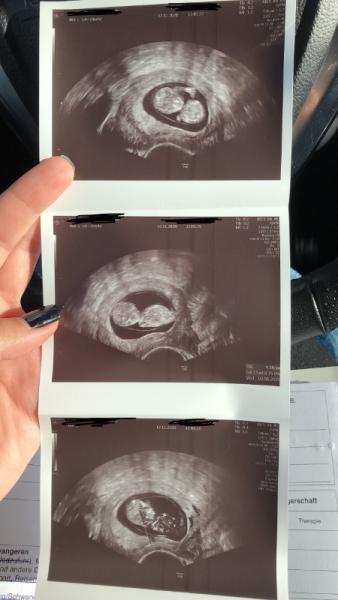

Ihr lieben, der Termin heute war wunderbar ! Mutterpass habe ich endlich und dem Baby geht es super! Das Herzchen schlägt fleißig, es bewegt sich sehr aktiv (hat uns gewunken) und als der Ultraschall zu nah kam, hat es sich sogar weg gedreht so aufregend. Am 26. habe ich das 1. Trimester screening. Ich wurde von 10+4 auf 11+2 datiert. Anbei noch ein schönes Bild

Bild zu Endlich !! 💥 - Forum für Juni - Mamis